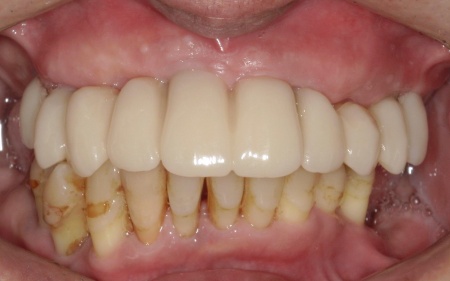

①上の歯7本、右下の奥歯2本を抜歯する。上あごには抜歯と同時に4本のインプラントを埋め、その上に10本分の仮歯を取り付けるオールオンフォーを行う。

インプラントの種類には、あごの骨と結合する力に優れたオステム社のETⅢを採用。インプラントが骨にしっかり定着するまでの間は、通常のインプラントよりも細い暫間インプラントを一時的に併用して仮歯を支える

②インプラントが安定したことを確認してから、仮歯を外して最終的な人工歯を装着する

最後に、残っている下の歯としっかりと噛み合っていることを確認し、治療を終了しました。